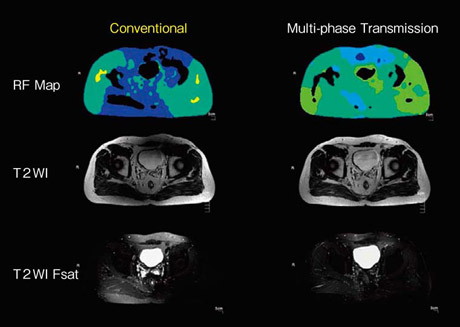

3Tでは,特に躯幹部において,RF磁場の不均一が1.5Tに比べ強くなる。この解決策として,送信するRFの位相と振幅をコントロールすることがキー技術になっている。Multi-phase Transmissionでは,より高い精度で位相と振幅を制御するために,従来1台であった送信RFアンプを2台用いて送信する。これによって位相と振幅を高い精度でコントロールすることで,躯幹部において不均一であったRF磁場をより均一にすることができ,より均一な画像を得ることができる(図2)。

図2 従来送信方式とMulti-phase Transmissionの画像比較

RFの位相と振幅をコントロールすることでRF磁場の均一性の向上が可能になり,画像の均一性が向上する。